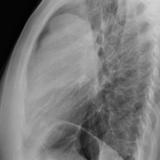

Case 8b Thymoma Lat

Date: 03/27/2009

Views: 14094